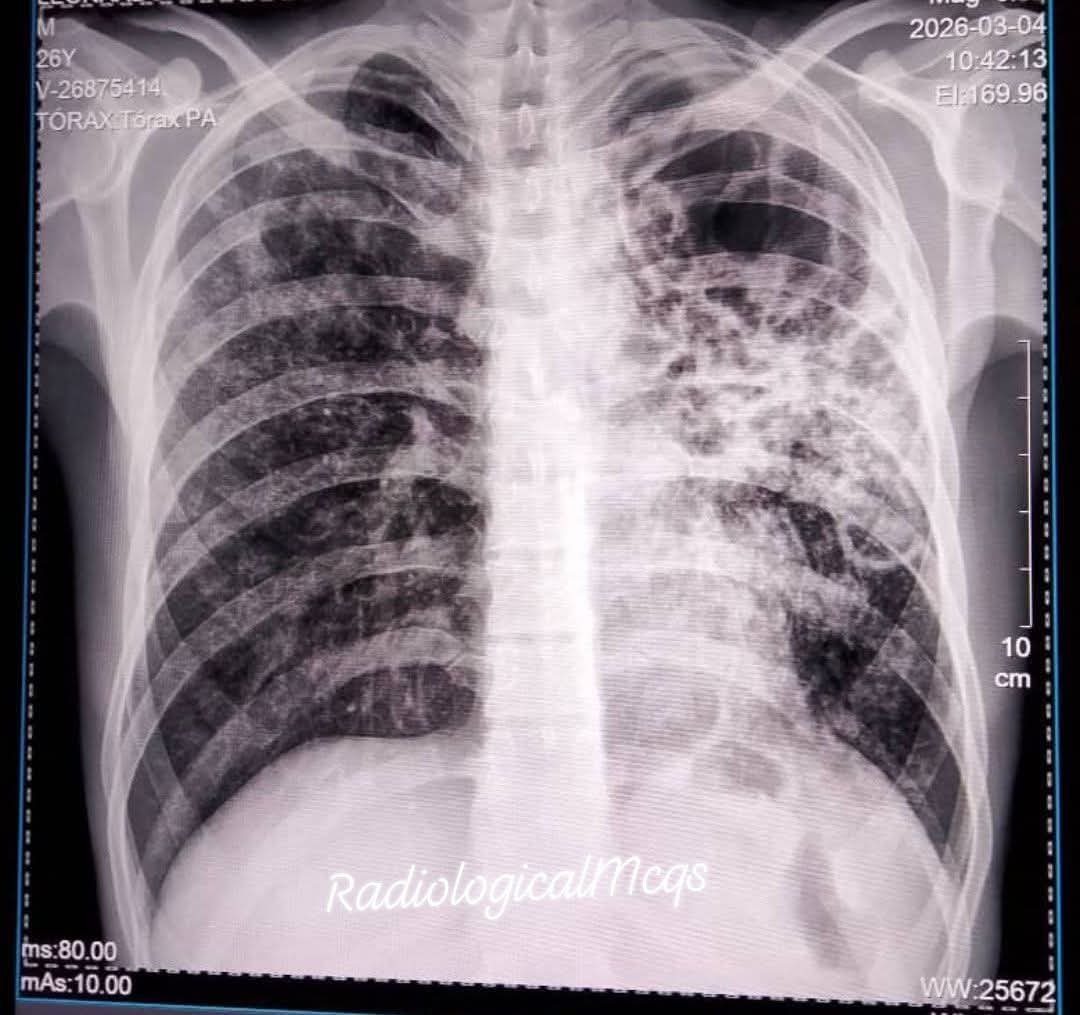

53 years old man Presented with chronic cough night sweats Associated with loss of weight.chest x ray was performed what are the findings and diagnosis? #radiographer #wellness #xray #health #diagnosis #radiology #pulmonology #respiratory @Dr_Chibuike_M @Dr_Shiv_kumar_

albertoortegana's tweet image. 53 years old man Presented with chronic cough night sweats Associated with loss of weight.chest x ray was performed what are the findings and diagnosis?

#radiographer #wellness #xray #health #diagnosis #radiology #pulmonology #respiratory